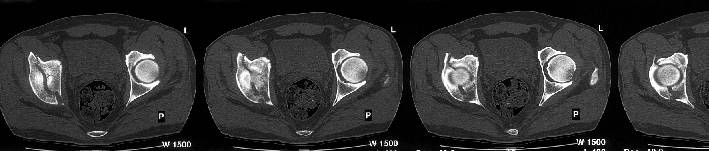

The iliac oblique reveals a displaced fracture of the posterior column, and it appears that the femoral head is not congruous with the acetabulum.

AP, obturator oblique films and a CT scan will better reveal the extent of the injury.

The CT scan confirms what the iliac oblique showed - the acetabulum is incongruous, and the femoral head is following the caudal piece medially. The other thing the femoral head is doing is grinding up against that displaced fracture. This is going to lead to erosion of the femoral head cartilage, and rapid onset of post-traumatic arthritis.

Yes it does. The CT scan reveals a fracture through the weight bearing dome.